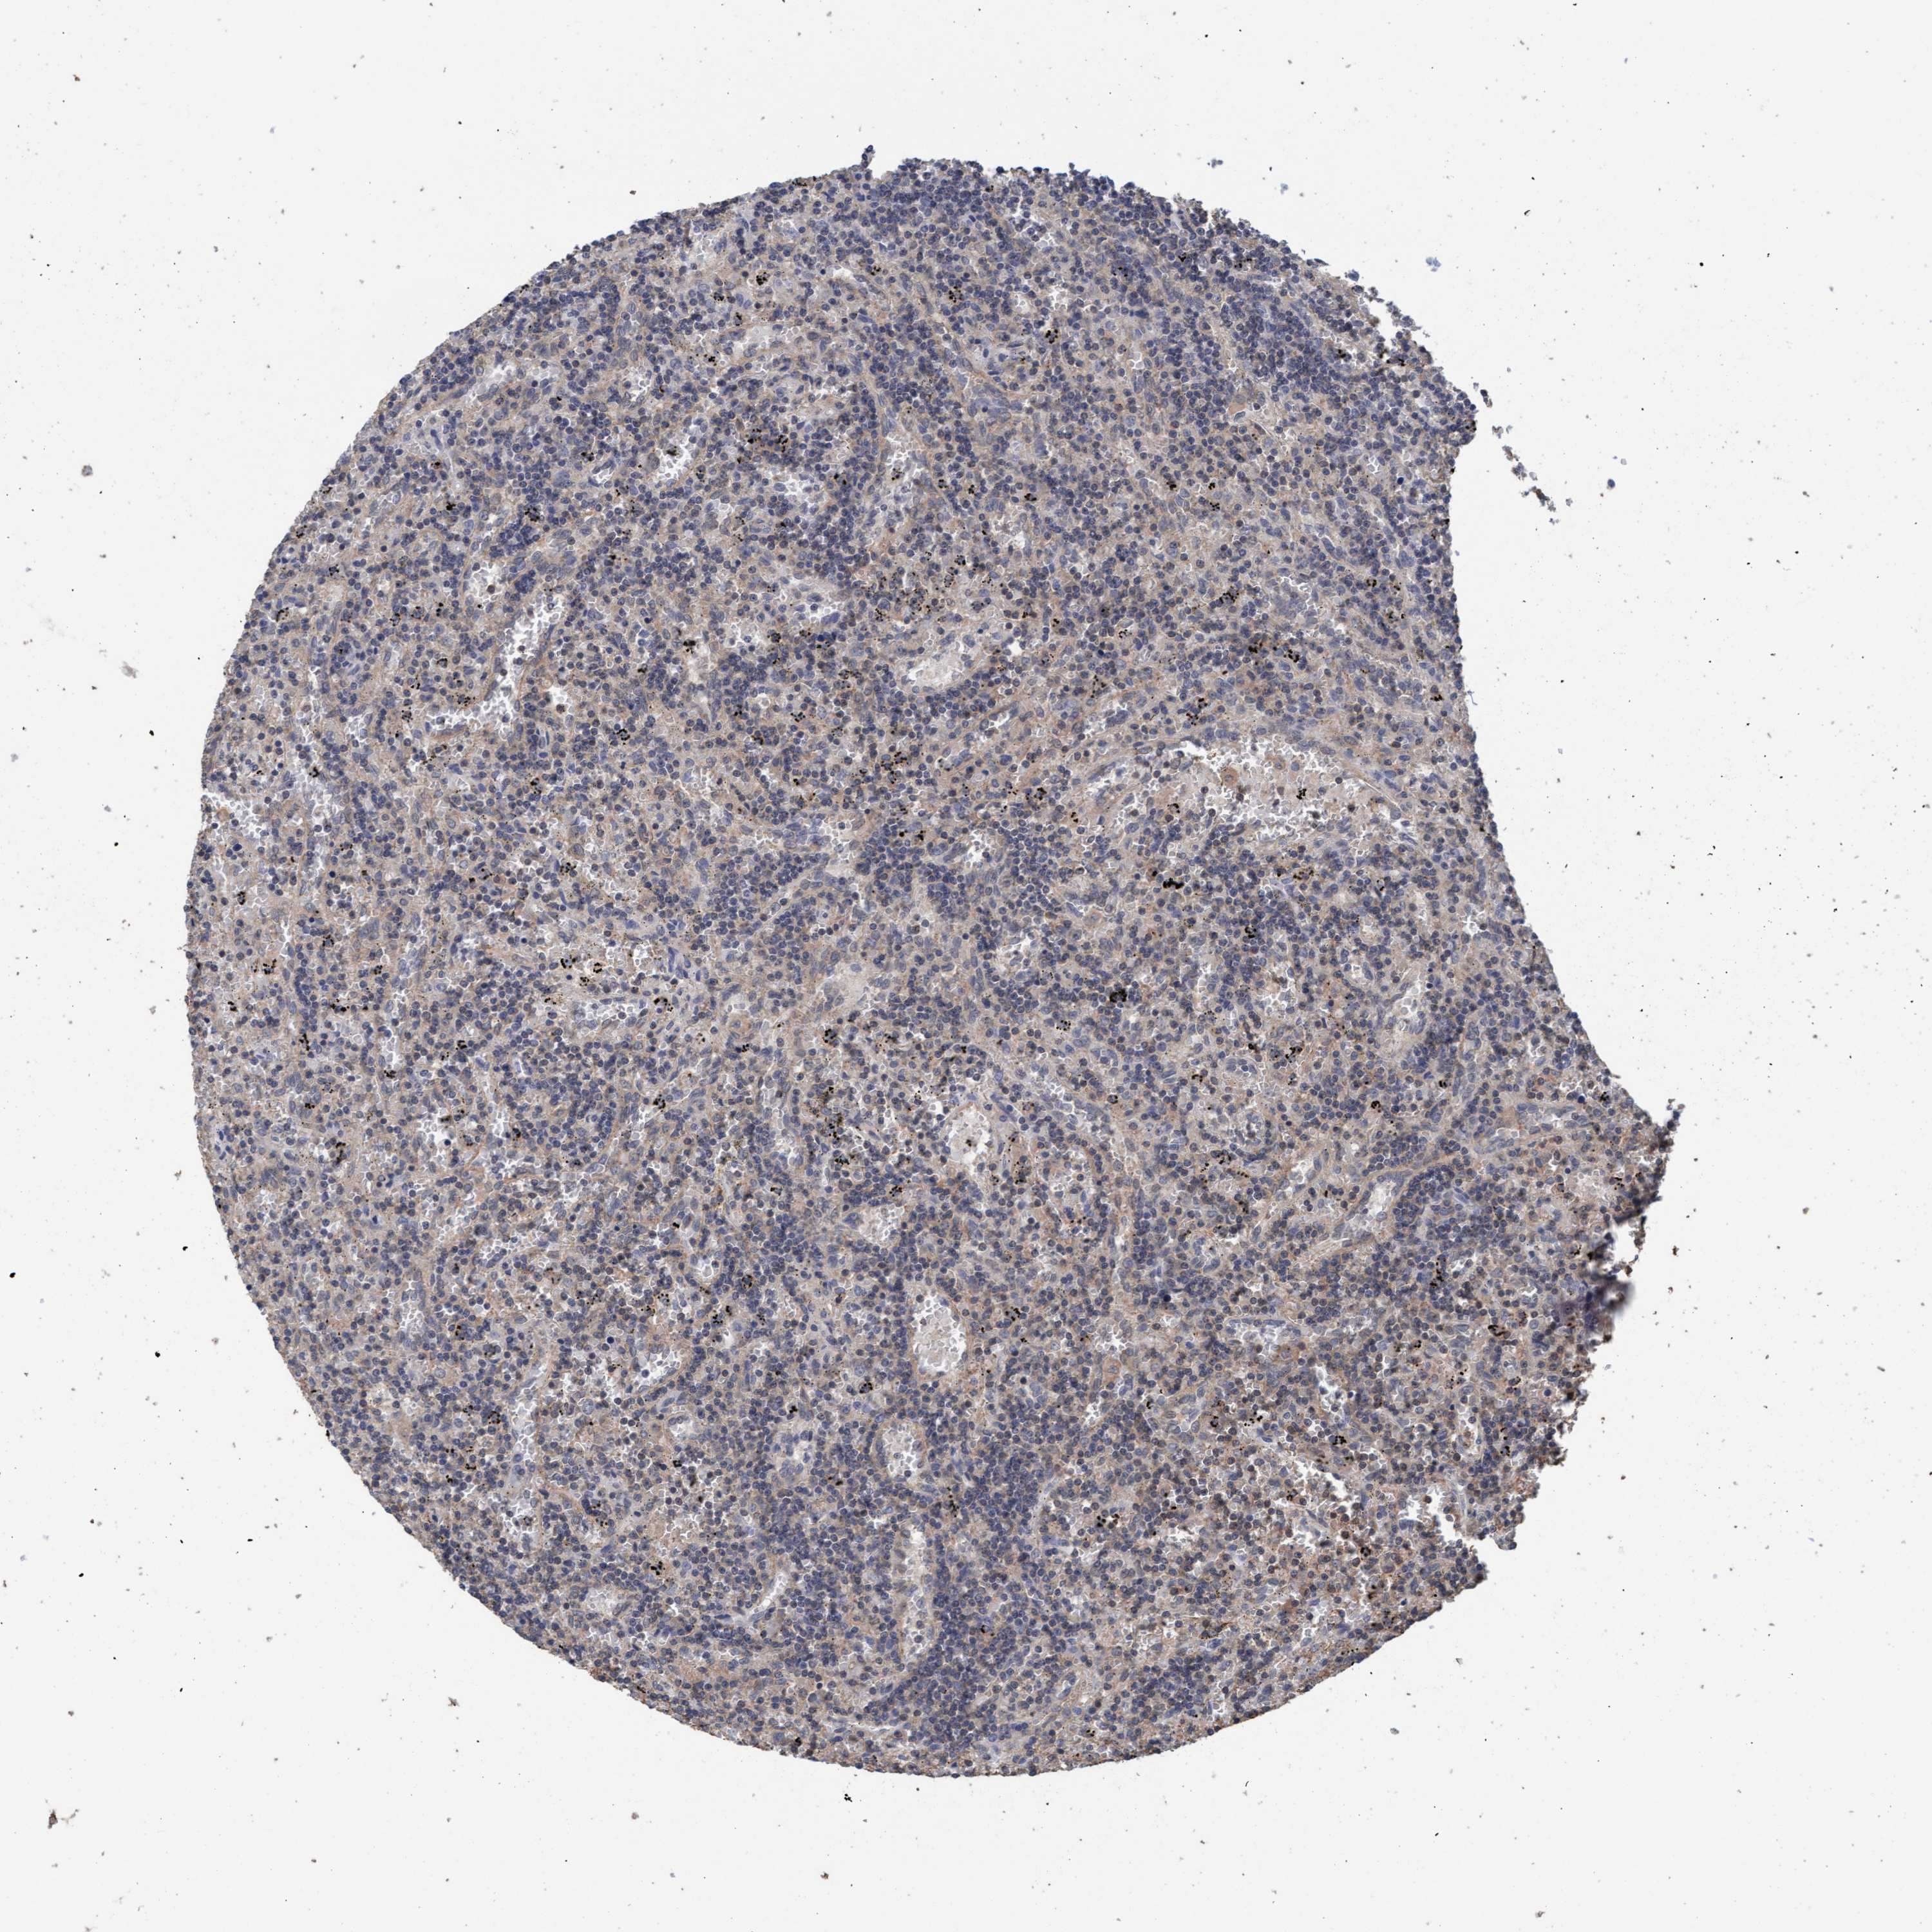

CANCER LYMPHOMA Show tissue menu

LYMPHOMA - Protein expressioni

A mouse-over function shows sample information and annotation data. Click on an image to view it in a full screen mode. Samples can be filtered based on level of antibody staining by selecting one or several of the following categories: high, medium, low and not detected. The assay and annotation is described here.

Each image is clickable and will lead to virtual microscopy that enables deeper exploration of all samples and also displays staining intensity scores, fraction scores and subcellular localization as well as patient and tissue information for each sample.

Antibody HPA022997

Antibody CAB011205

Hodgkin's disease, NOS

Malignant lymphoma, non-Hodgkin's type, High grade

Malignant lymphoma, non-Hodgkin's type, Low grade